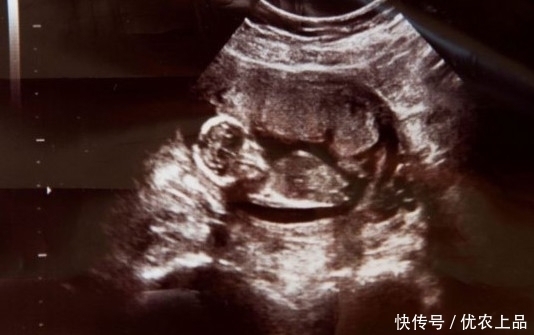

在爱尔兰的基尔代尔郡有这样一个神奇宝宝,她妈妈经过人流之后她居然还能存活下来,顽强的小生命力不得不让人倍感佩服。

这个神奇宝宝的妈妈叫做米歇尔,在米歇尔怀有她第六个月的时候,米歇尔出现严重大出血,去医院检查被医生告知这种情况会出现感染,因此肚子里的孩子只能进行人工流产。

米歇尔按照医生指示,服用药物进行流产。就在服用药物之后,她以为孩子流掉了,出血情况也没有再出现。就在她回到医院进行复查的时候,医生告诉她子宫内还残留血凝块,必须要进行手术将这些血块拿出。

【胞胎姐妹被妈妈用药物流掉,她却在母亲腹中安稳存活】在手术前,医生在她腹部监测到不属于她的另外一个心跳,原来米歇尔怀的是双胞胎,其中一个宝宝被服用药物流掉了,另一个却奇迹般的活了下来。

米歇尔把她生了下来,取名梅甘。